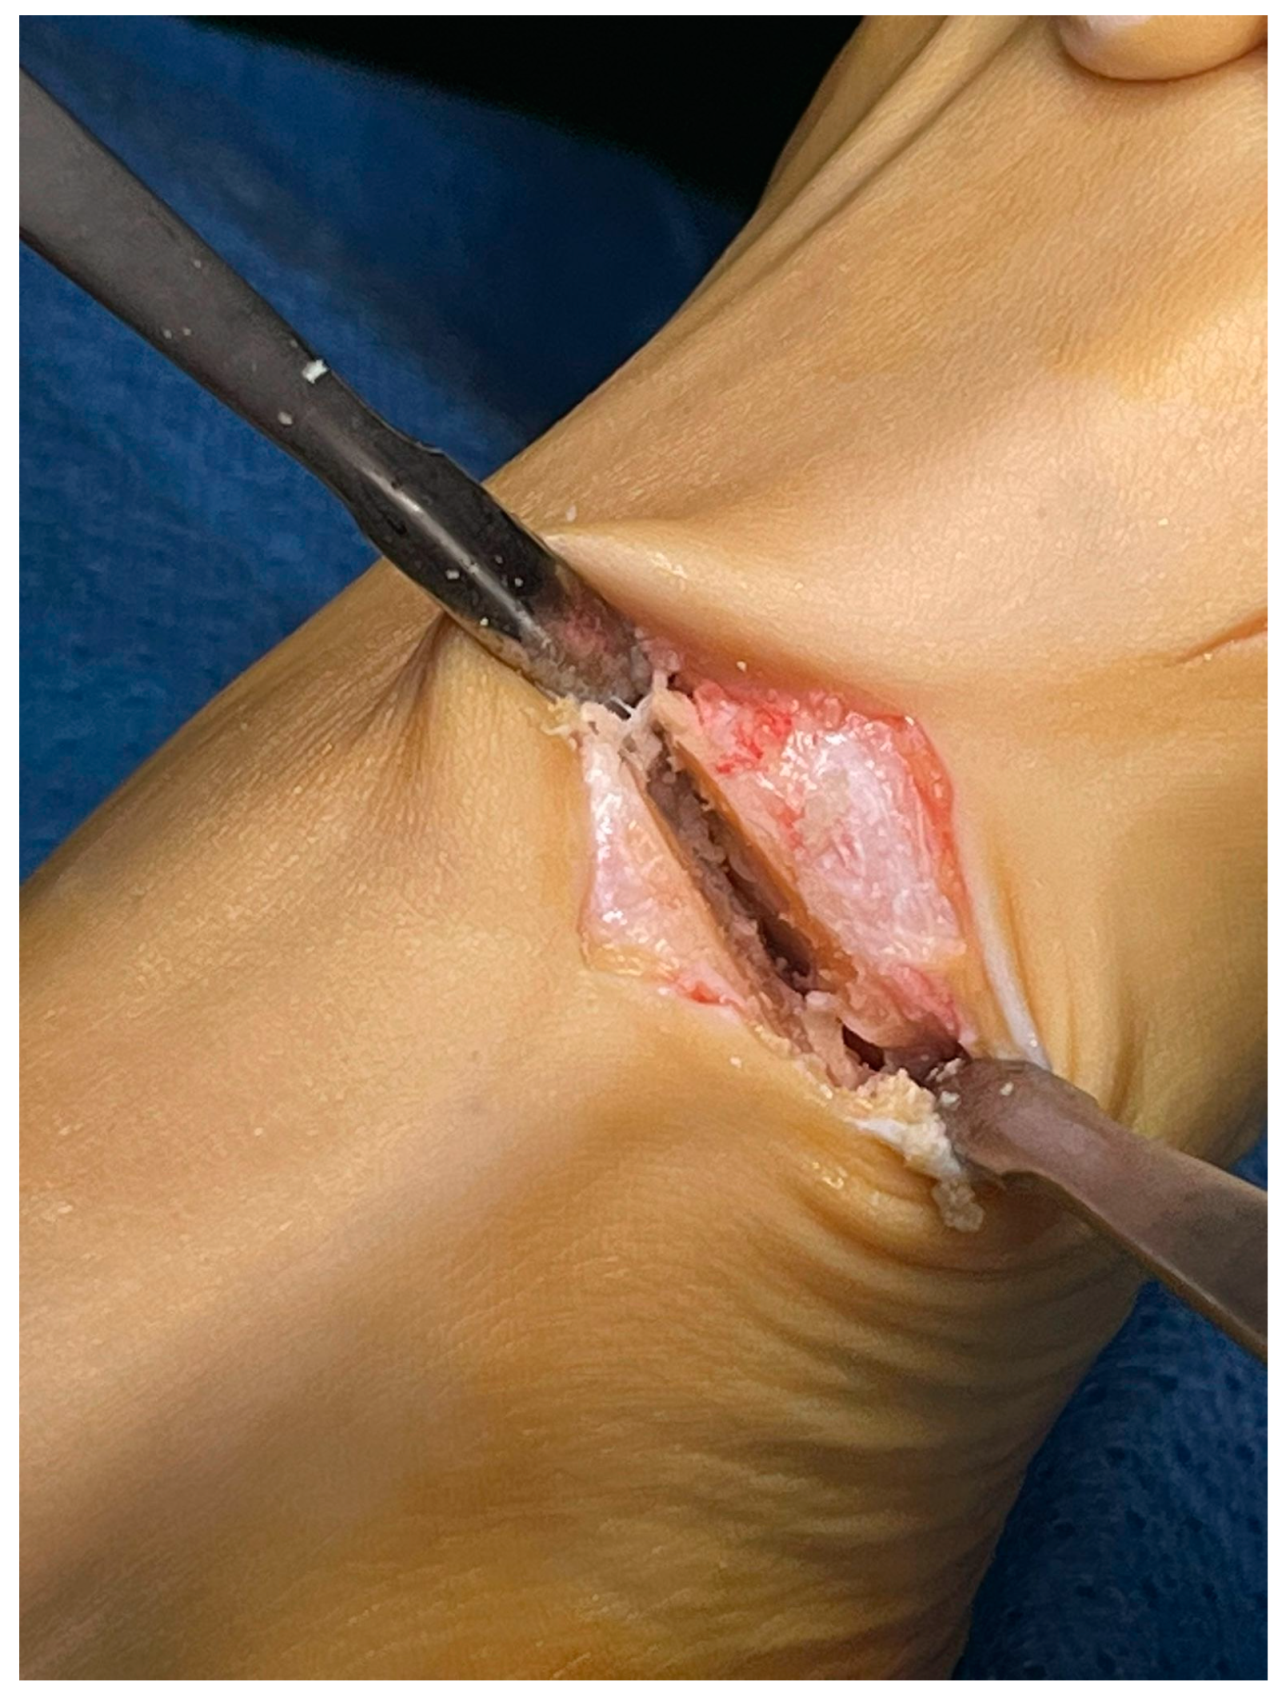

Minimally Invasive Lapidus Arthrodesis Associated with Distal Osteotomy of M1: A Combined Procedure for Hallux Valgus Correction

2. Materials and Methods